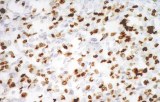

Primary antibodies for immunohistochemistry CE/IVD - Pediatric pathology

Perinatal/paediatric pathology is a medical subspecialty with particular expertise in diseases affecting the placenta, fetus, infant and child. Although many conditions that affect adults also affect children, pediatric pathology includes many conditions found only in patients younger than 18 years of age. One group of conditions involving the infant population is congenital anomalies. A malformation is a congenital anomaly due to an intrinsic defect in development. A disruption occurs when a normally developing organ is secondarily damaged by another process. A sequence is a collection of several anomalies, all of which are due to one malformation, disruption, or deformation. Finally, a syndrome is a group of related anomalies. An other group is the pediatric cancers or childhood cancers. Childhood cancers include many that also occur in adults. Leukemia is by far the most common, representing about 33% of childhood cancers, brain tumors represent about 25%, lymphomas represent about 8%, and certain bone cancers (osteosarcoma and Ewing sarcoma) represent about 4%.